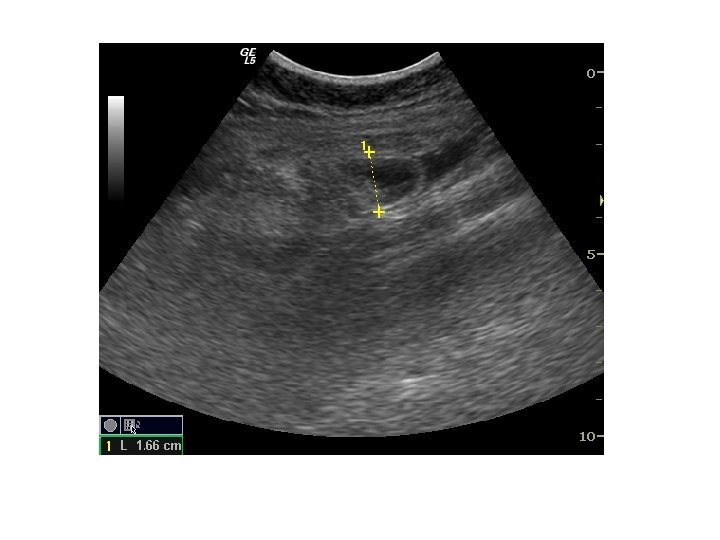

Questions • Describe the ultrasound finding

• What did you think about the nature of material that caused the

• What did you think about the nature of material that caused the problem? (Metal, glass, plastic or wood) Why?

• What were the ultrasound findings? • What was the diagnosis? • What

• What were the ultrasound findings? • What was the diagnosis? • What were the ultrasonic features of acute appendicitis? • Name 3 clinical signs of acute appendicitis • Name one scoring system for acute appendicitis